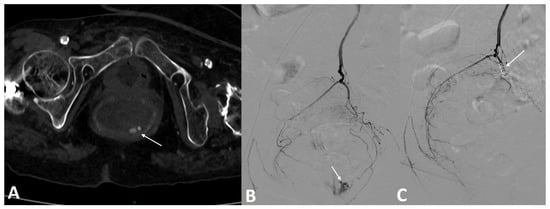

2.4. Transarterial Embolization Methods and Techniques

3.4. Post-Angiography Course